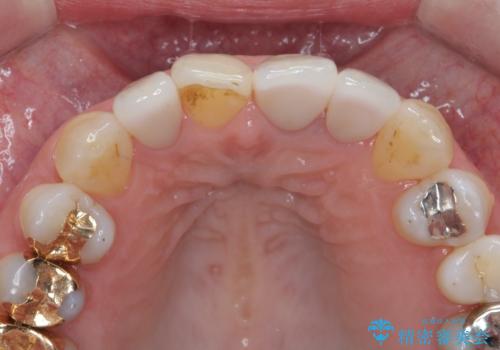

- 前歯のクラウンの歯肉の位置が年々変化し、歯ぐきのフチが黒くなってしまった、綺麗にしたいと希望されて来院されました。

装着されているセラミッククラウンを除去したのち、現在の歯ぐきのラインにしっかりと合う精度の高いオールセラミッククラウンを作製していきます。

周囲の歯に調和したセラミッククラウンを作製し、審美性を大幅に向上させることができました。